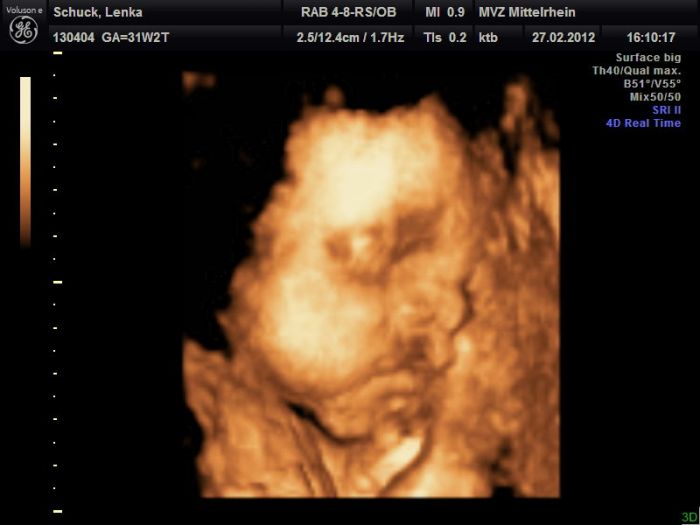

Tak dnes to vyšlo :)) Sice ne úplně dokonale, ale byl to poslední pokus, tak lepší než nic :))) Malej už je holt moc velkej...

Leno,moc hezký fotečky,je vidět,že u je mu tam už těsno.Jinak Maruško už mám13 kg nahoře.

Lenulko ten je krásnej

Dík holky :)) Ale zase jsem měla o 2 kila míň, než posledně :D Já furt hubnu a z malýho roste otesánek :D